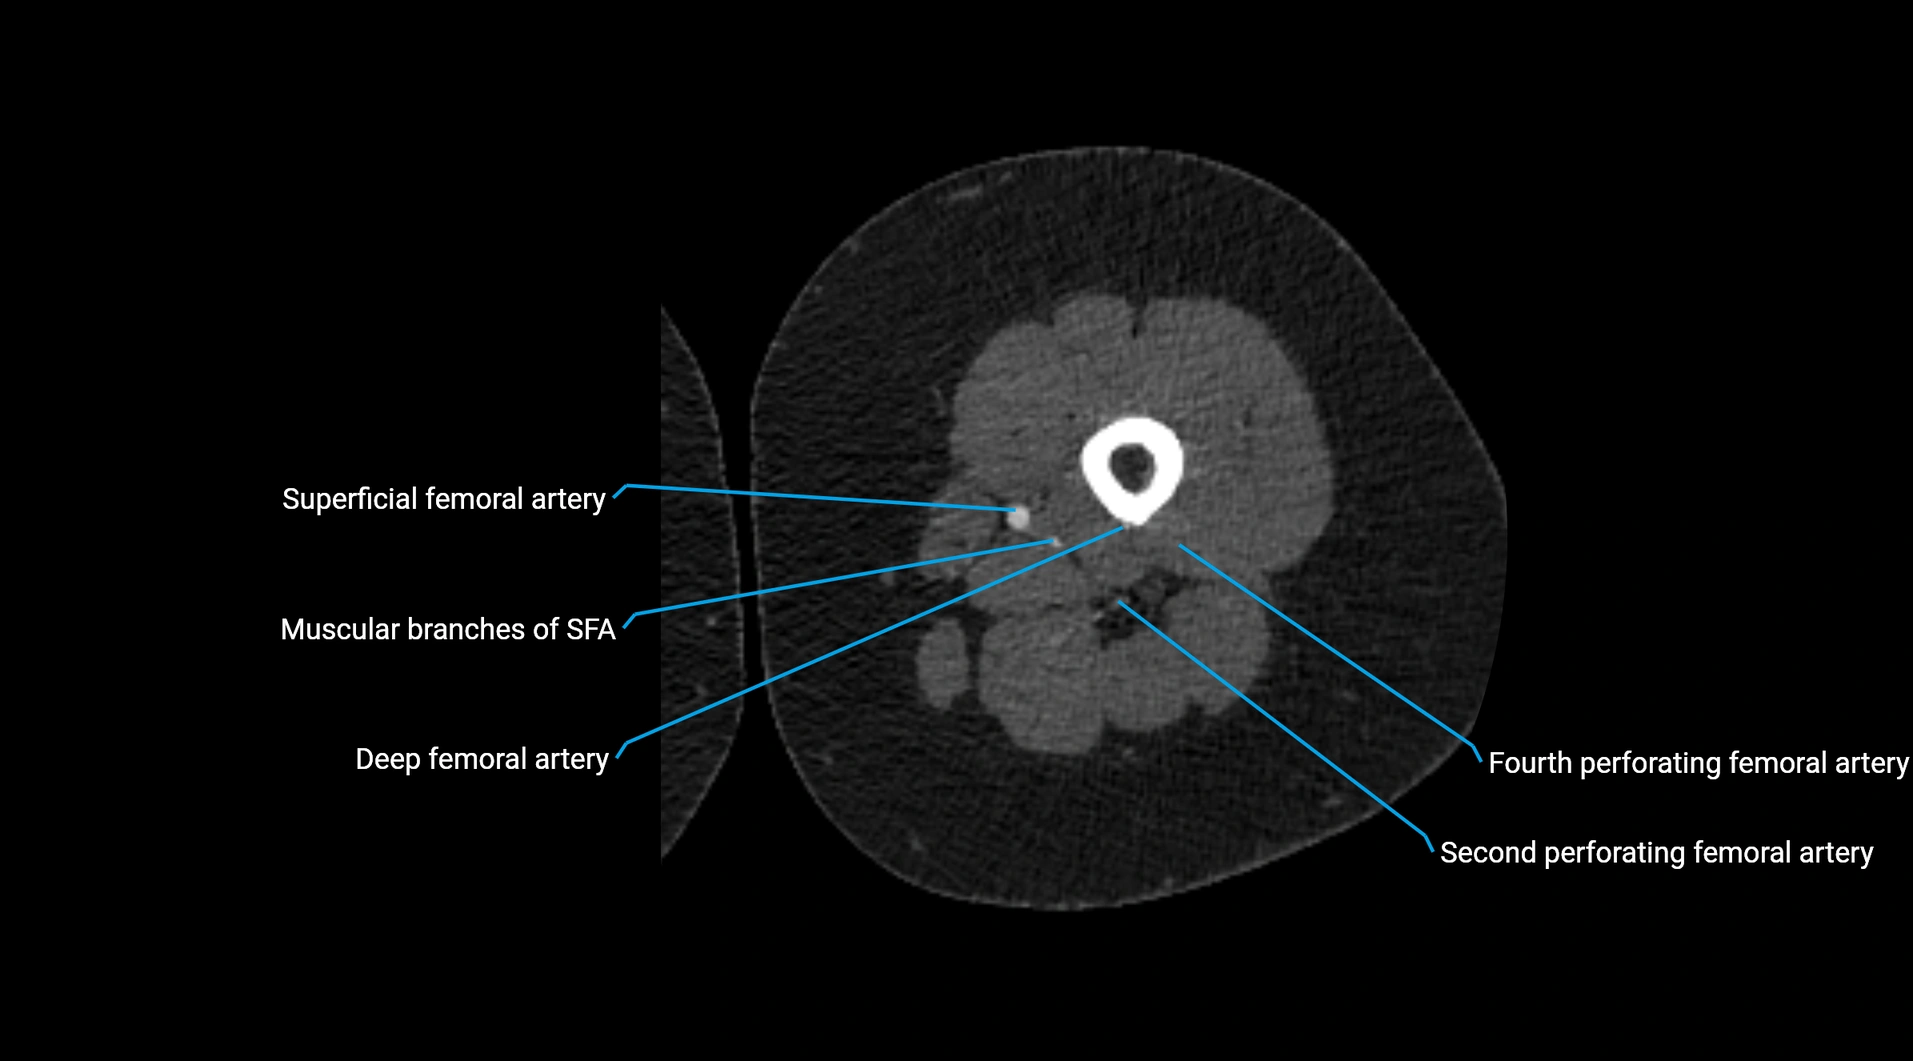

CT images

image